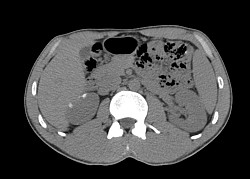

Брюшная полость и забрюшинное пространство